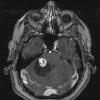

NEOPLASMS (MESENCHYMAL, NON-MENINGOTHELIAL)

Hemangioblastoma (9)